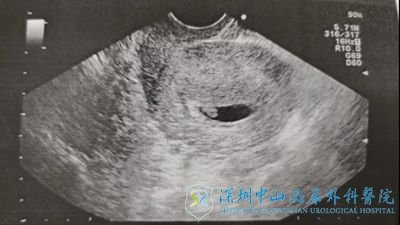

2019年3月,张女士第三次取卵,获卵7个,成熟卵子6个,移植两个胚胎(一个2级胚胎,一个3级胚胎)其余胚胎碎片多,质量差,废弃。移植后13天抽血HCG显示怀孕,移植后一个月B超监测显示宫内单孕囊单胎存活。目前张女士妊娠满10周,到当地医院产检建档。